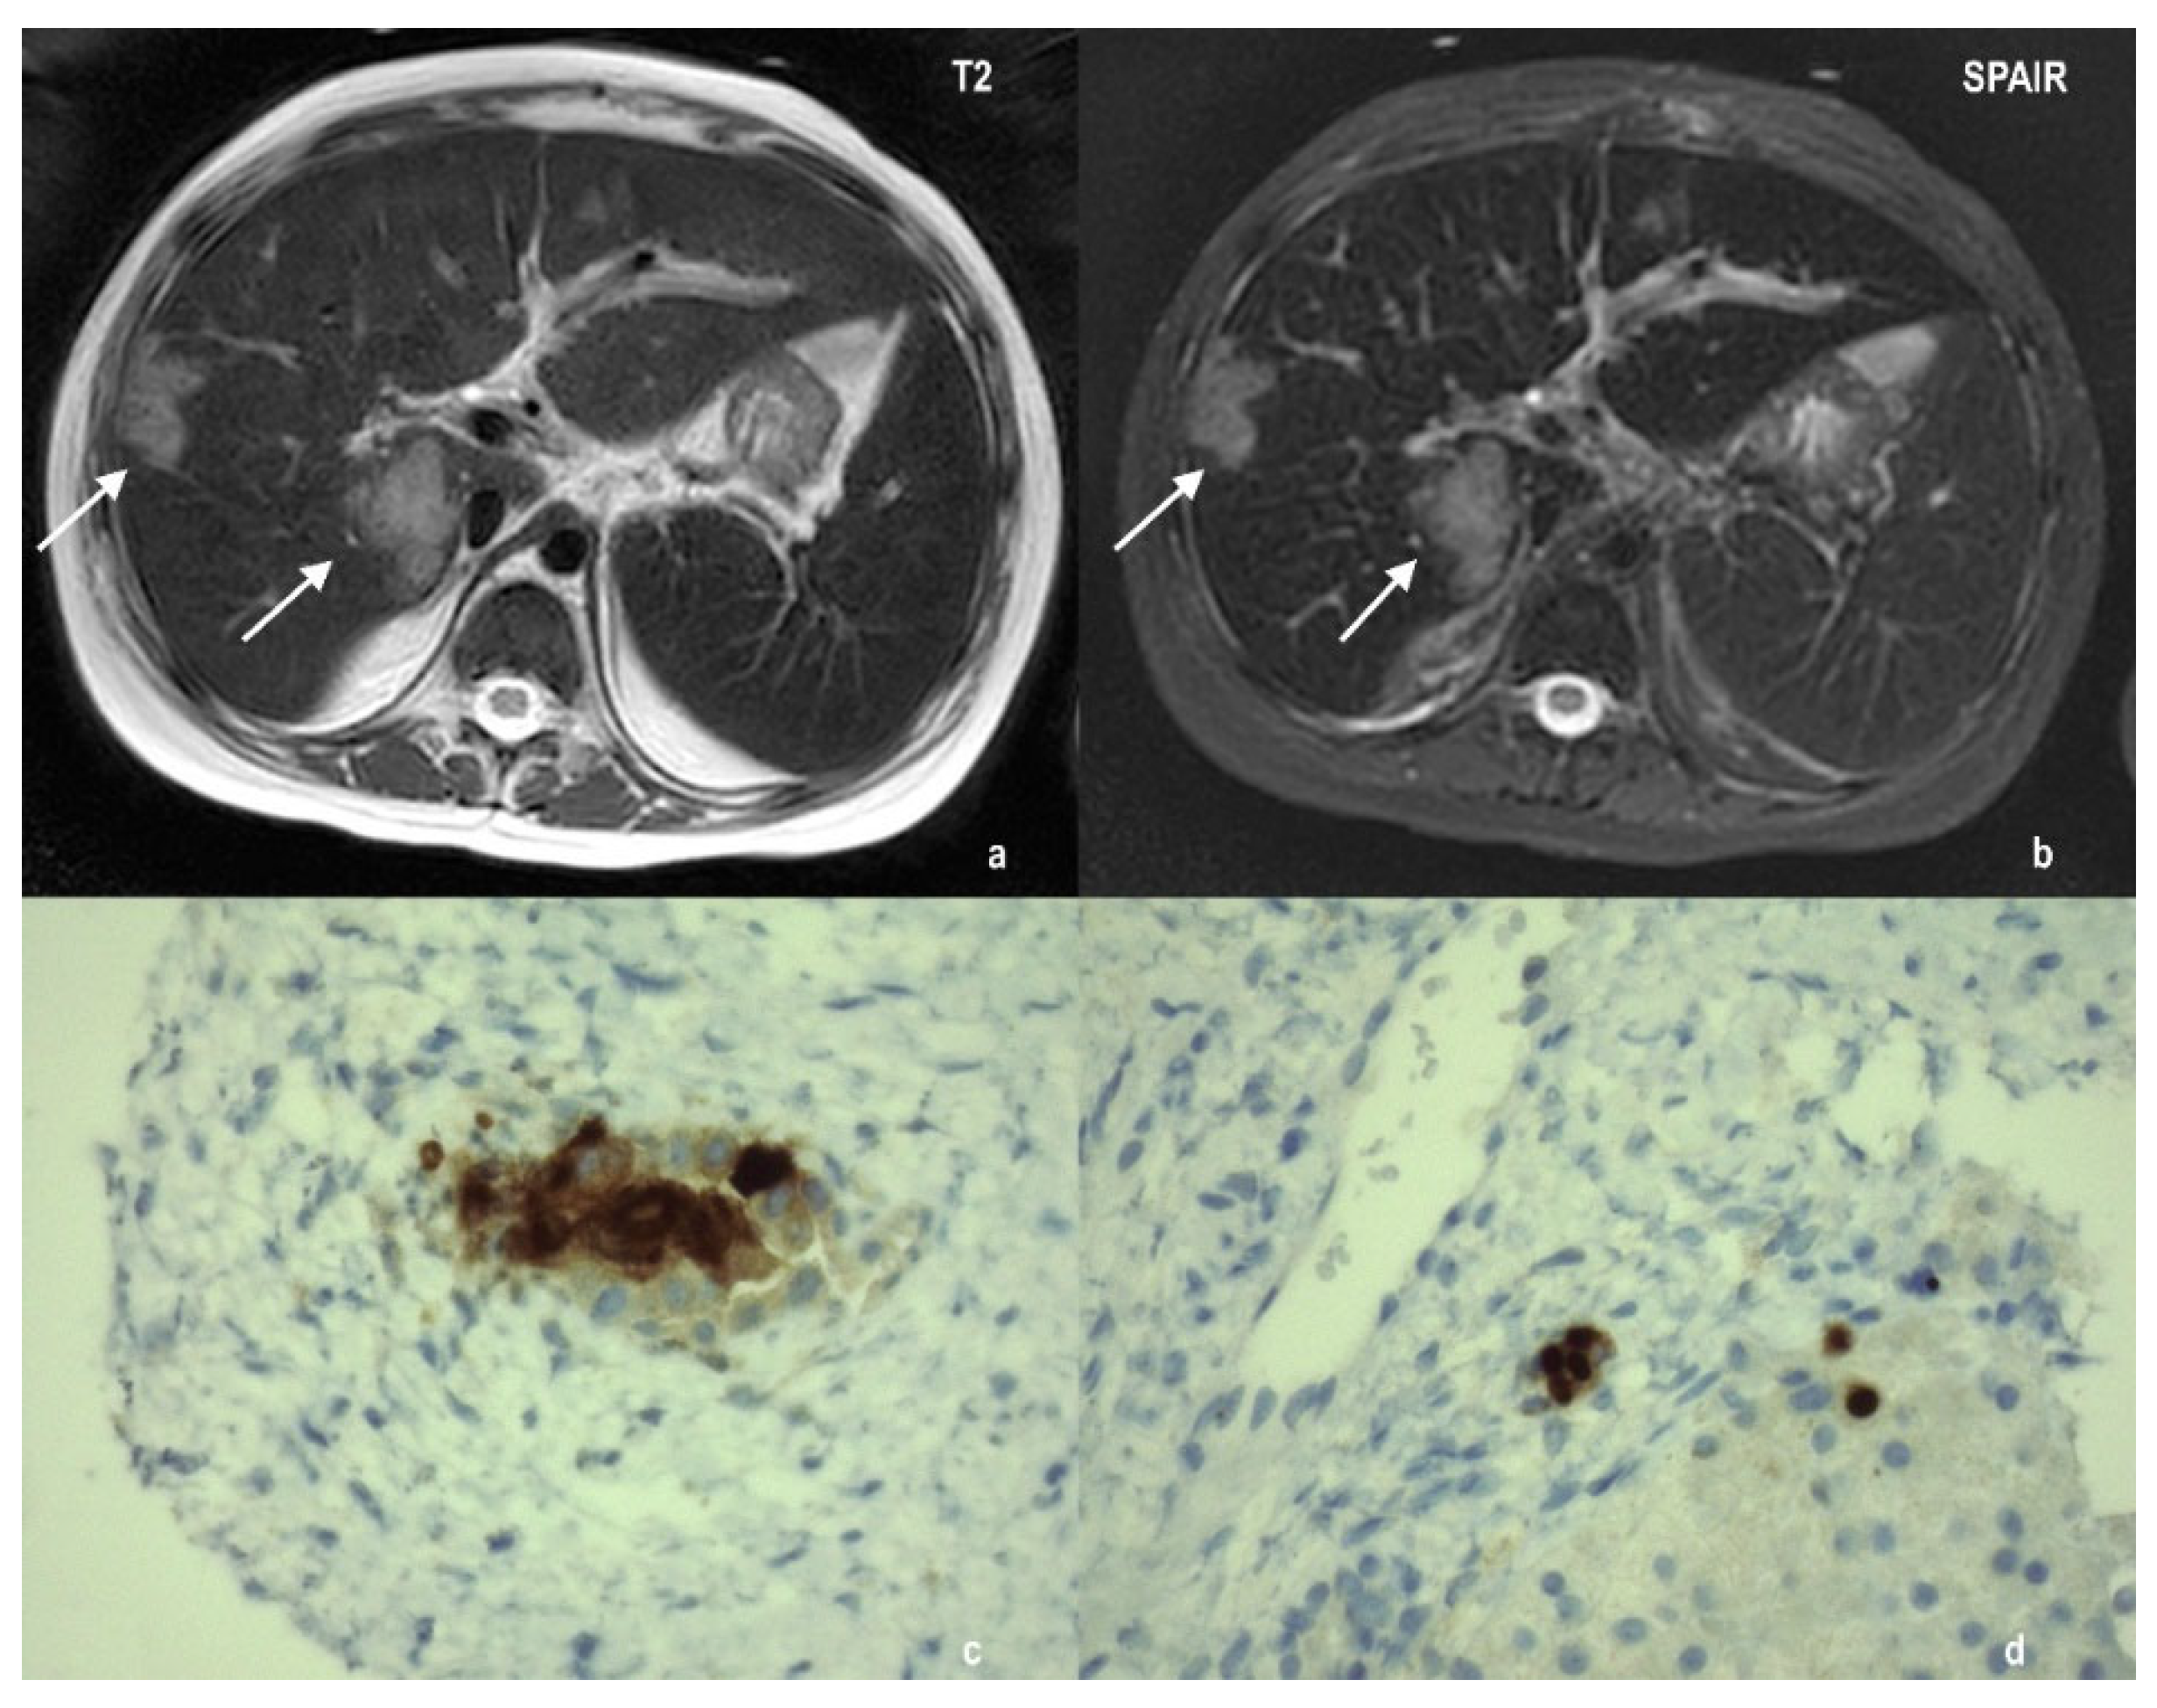

2.2. Case 2

2.3. Case 3